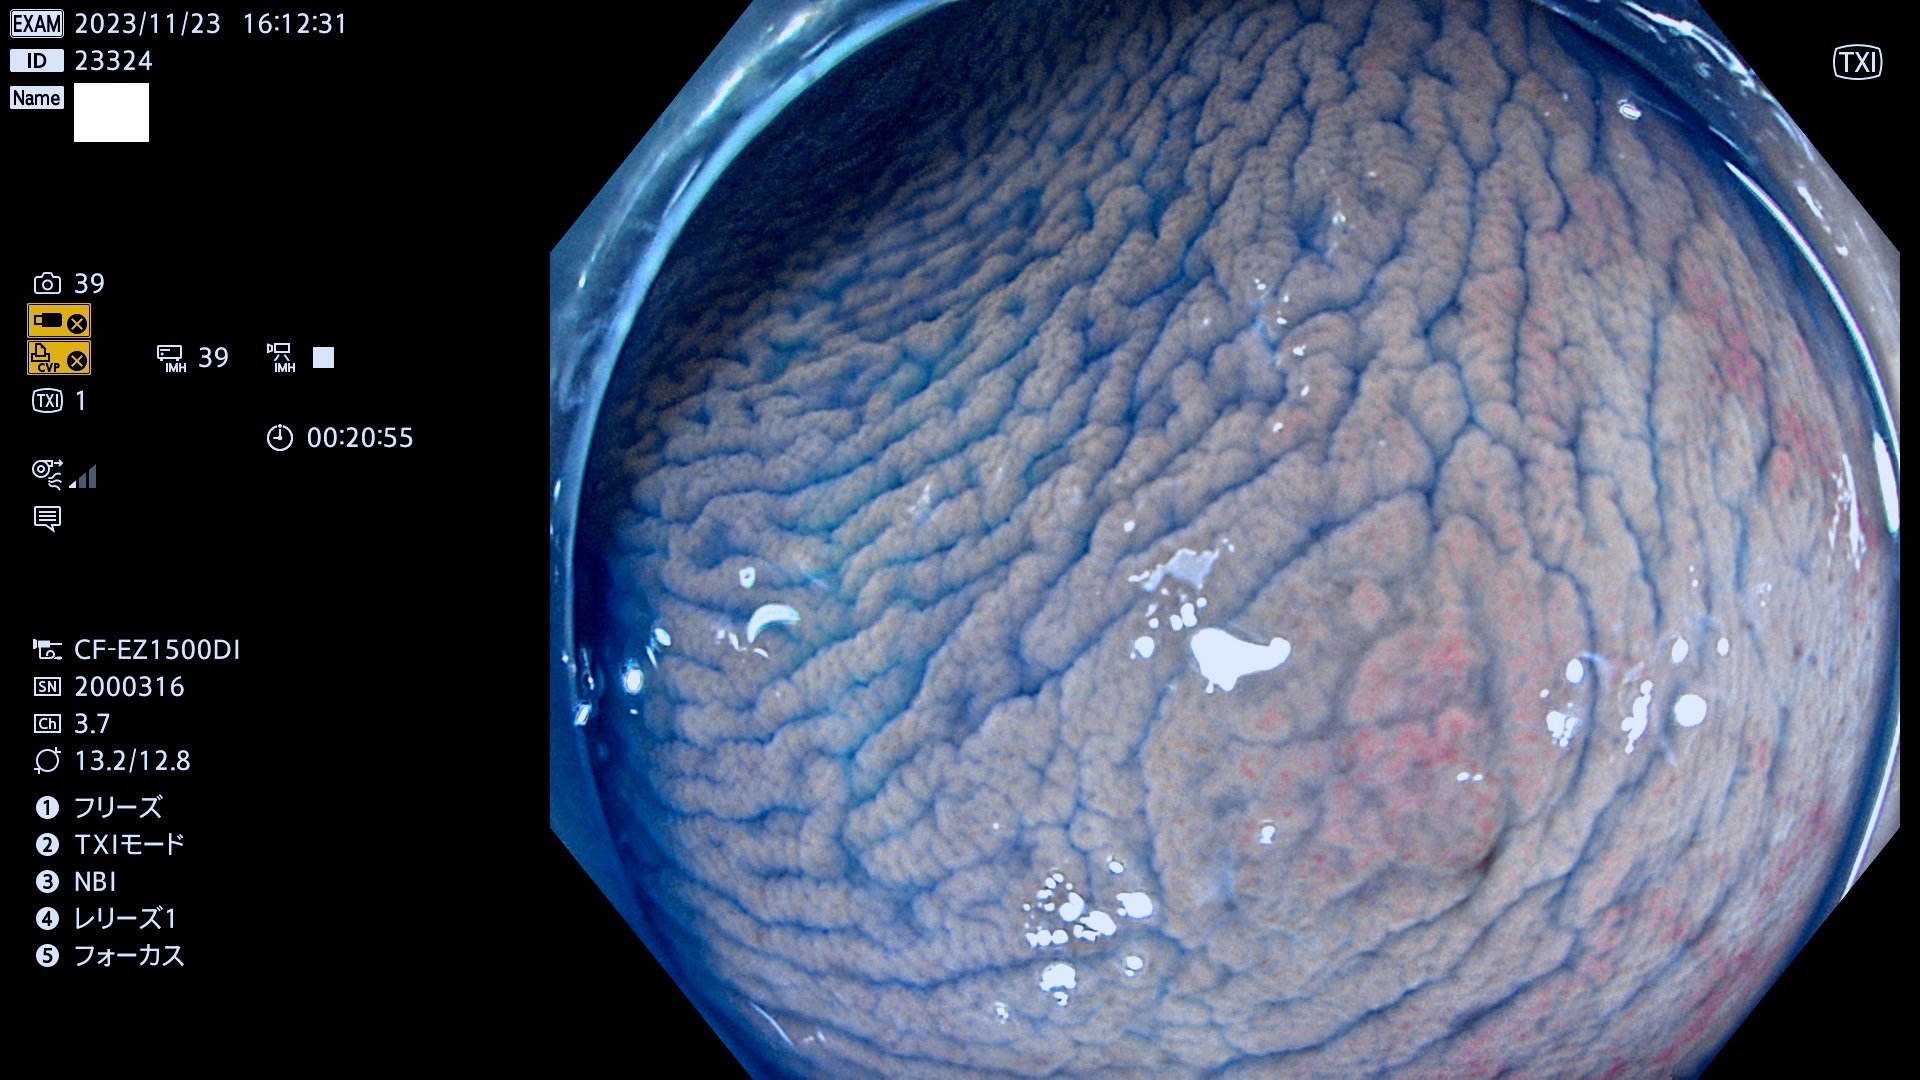

表面型腺腫(Flat Adenoma)の中で、完全に平坦な物をUb、陥凹している物をUcと呼びます。平坦隆起型(Ua)よりも、発見が難しく危険な病変です。このタイプは「内視鏡後・大腸癌の重要犯人」であり、この発見率は「腺腫発見率」よりも、重要な意味があります。

毎週の検査(木・金・土・日)に発見されたUb、Uc型・腺腫を、その週の日曜の夜にUPし1週間、提示します。

抽出の対象期間 2023年11月23日(木)〜11月26(日)の4日間(48件の検査)8件